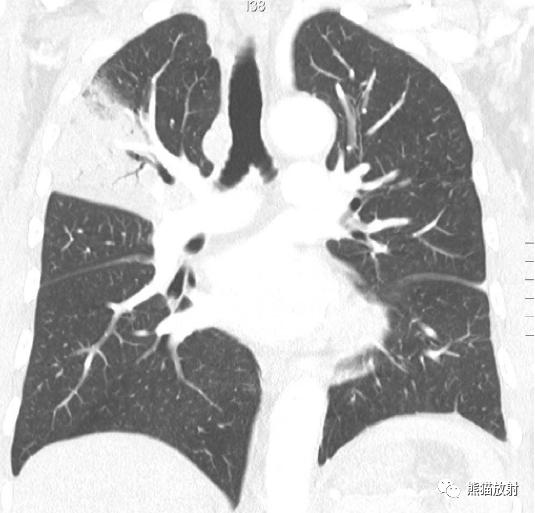

↑ 大叶性肺炎 Lobar pneumonia

36岁男性,肺炎链球菌肺炎。冠状重建CT显示右肺上叶的均匀局灶性实变。实变影中可见支气管充气征(air bronchograms)。